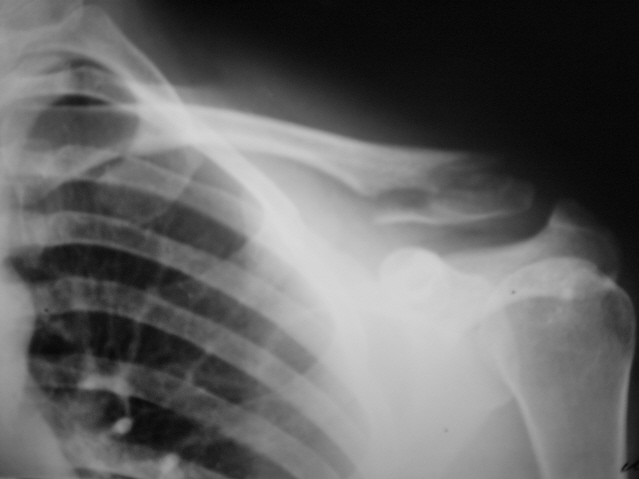

Травма. Перелом ключицы.

Травма. Пациент направлен в рентгеновский кабинет врачом хирургом.

Валентин Львович, а какой механизм травмы? смущают контуры отломков - нет ли здесь очагов деструкции с патологическим переломом?

Имхо травматический перелом.

Механизм не скажу, врать не буду. Но этот случай был в моем "запаснике" и еще не выставлялся. Решил выставить, хотя перелом давно весьма успешно консолизировался и даже без деформации ключицы.